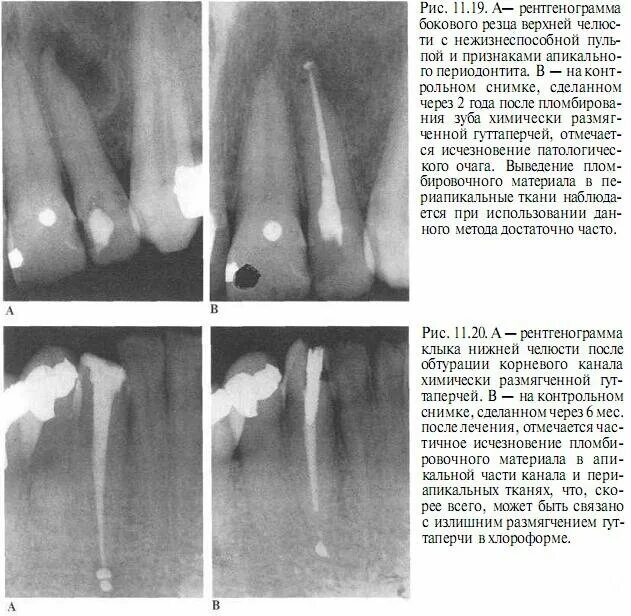

Ретроградное пломбирование корневых